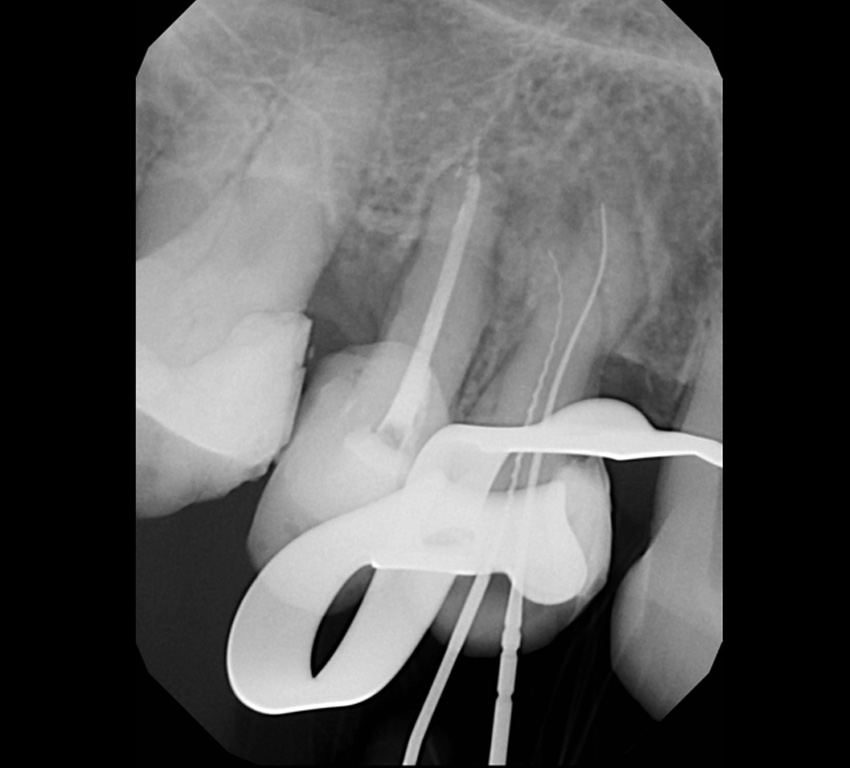

A gyökérkezelés eredményességének megállapítására a klinikai vizsgálaton kívül leginkább a képalkotó eljárások alkalmasak. A fog gyökerét vagy gyökereit, és gyökércsúcsi területét monitorozó periapicalis röntgenfelvétel alkalmas a gyökértömés, a fogágy állapotának, valamint az idő múlásával a gyökércsúcsi elváltozások gyógyulásának megítélésére.

Sikeres gyökérkezelésnek mondható ha a fog panaszmentes, csúcsig érő, falálló, jól kondenzált, jól záró gyökértöméssel lett ellátva, megfelelő koronai felépítménnyel rendelkezik, a meglévő periapicalis elváltozás gyógyulást mutat.